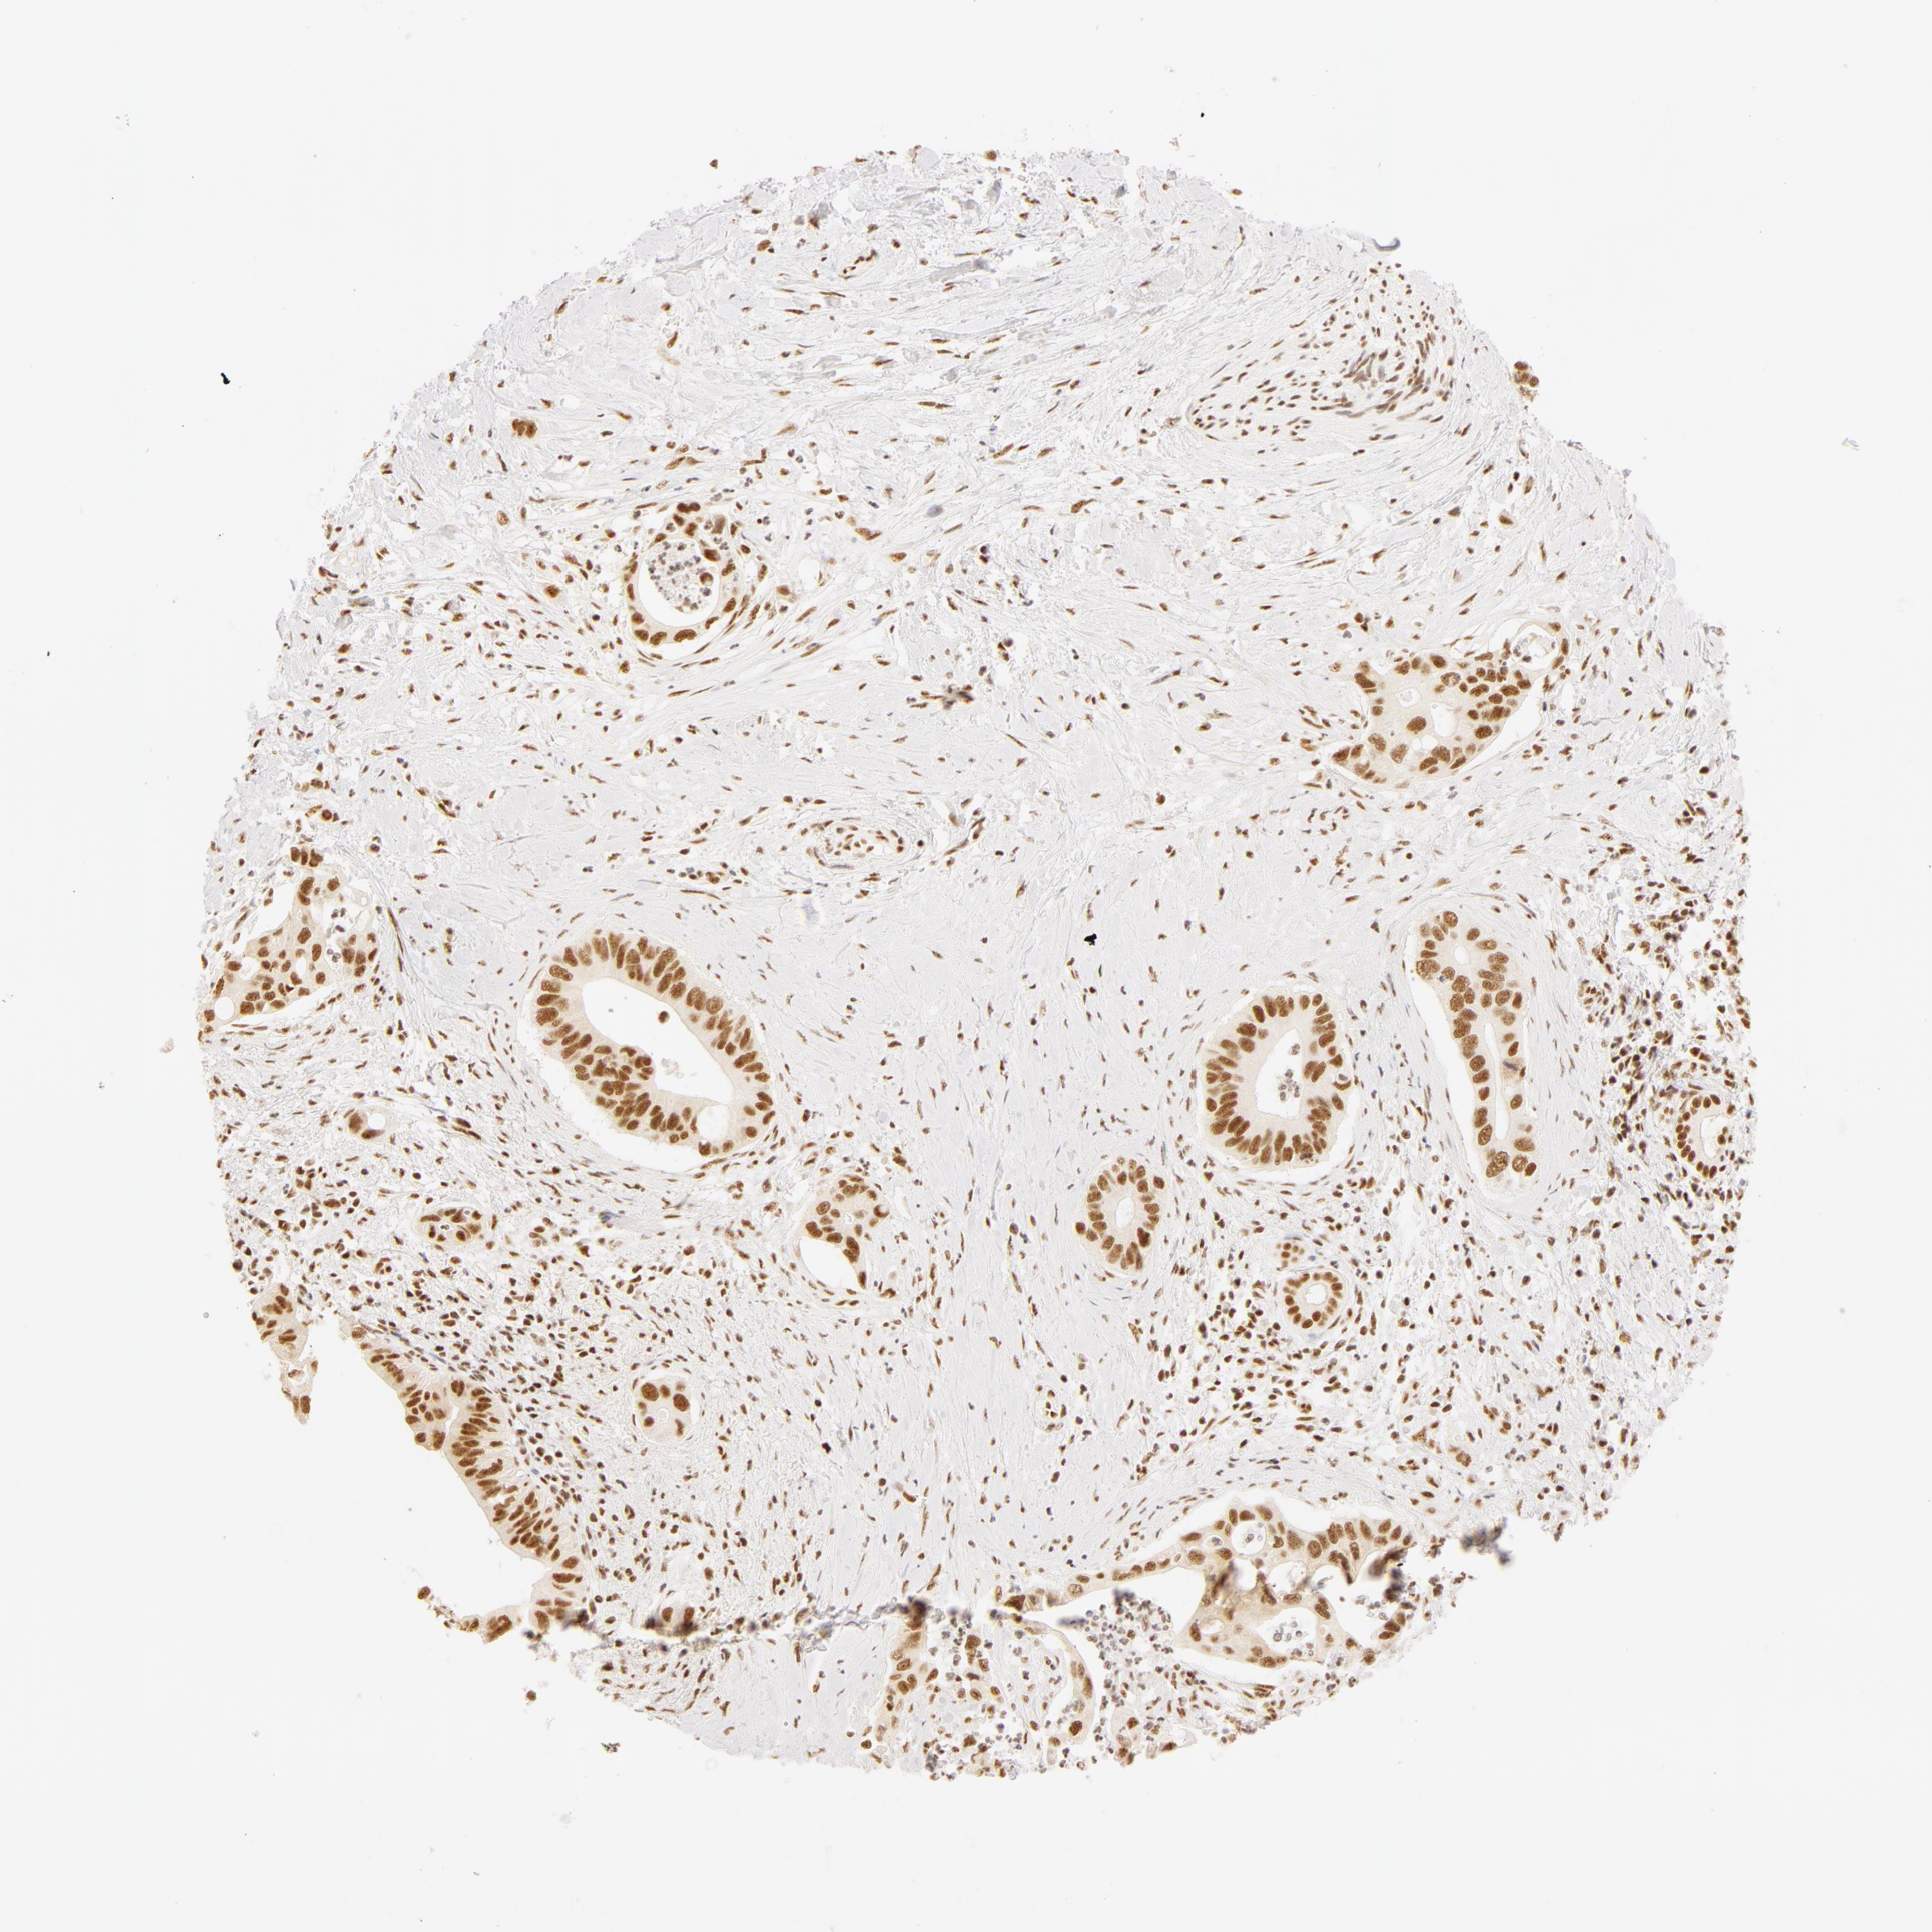

LIVER CANCER - Protein expressioni

A mouse-over function shows sample information and annotation data. Click on an image to view it in a full screen mode. Samples can be filtered based on level of antibody staining by selecting one or several of the following categories: high, medium, low and not detected. The assay and annotation is described here.

Note that samples used for immunohistochemistry by the Human Protein Atlas do not correspond to samples in the TCGA dataset.

Antibody stainingi

Antibody staining in the annotated cell types in the current human tissue is reported as not detected, low, medium, or high, based on conventional immunohistochemistry profiling in selected tissues. This score is based on the combination of the staining intensity and fraction of stained cells.

Each image is clickable and will lead to virtual microscopy that enables deeper exploration of all samples and also displays staining intensity scores, fraction scores and subcellular localization as well as patient and tissue information for each sample.

Antibody HPA001591

Staining

High

Medium

Low

Not detected

Intensity

Strong

Moderate

Weak

Negative

Quantity

>75%

75%-25%

<25%

None

Location

Nuclear

Cytoplasmic/membranous

Cytoplasmic/membranous,nuclear

Carcinoma, Hepatocellular, NOS

Cholangiocarcinoma